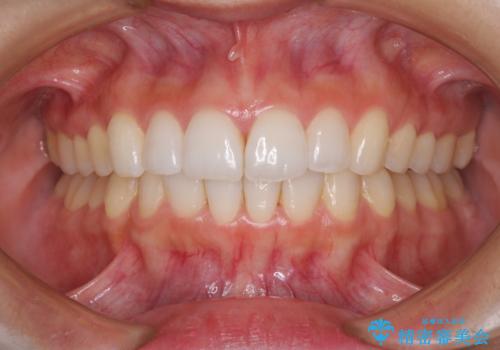

遠方から新幹線で通院 急速拡大装置とインビザラインによる矯正治療

- 小児矯正の頃から診察を行っている患者様です。

上顎骨の幅が下顎骨よりも小さいので、拡大装置により骨幅を広げて上下関係を改善し、その後インビザラインにて歯並びを整えることとしました。

上下の骨幅を改善したことで、スムーズに歯列矯正を行うことができました。

インビザライン治療開始直後に遠方に引っ越しをされたため、通院間隔が長くなり、治療期間が長くなりましたが、しっかりと治療を行うことができました。